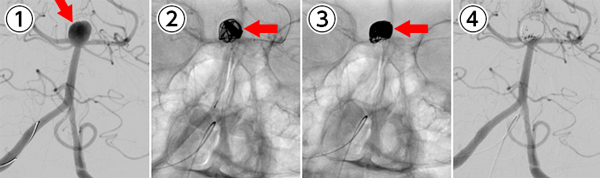

脳動脈瘤コイル塞栓術を施行。

①脳底動脈に長径10㎜の動脈瘤を認める(矢印)。

②カテーテル(細い管)から動脈瘤にコイル(細い金属)を挿入する(矢印)。

③動脈瘤に血液が流れ込まないように動脈瘤内にコイルを挿入。

④動脈瘤内に血液が流れ込まないようにして、再度動脈瘤から出血をすることを予防する。